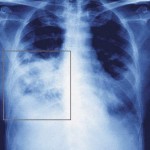

Let’s imagine you’re seeing a case of pneumonia, and you suspect (as is quite reasonable these days) that it is precipitated by H1N1 influenza.

Even though some of these pneumonias have been only H1N1, bacterial superinfection can and does occur — most commonly with our old friend S. pneumoniae, somewhat less so with group A strep, S. aureus (including MRSA, of course), and H. influenza.